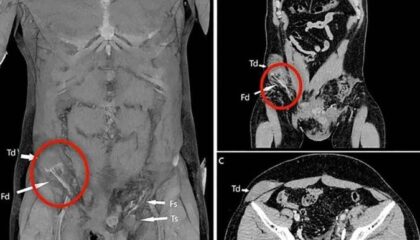

InternacionalApós acidente de moto, testículo de homem vai parar no abdômenDiagnóstico raro, segundo médicos, pode trazer consequências como perda de fertilidade, disfunção endócrina e malignidade futura Reprodução/BMJ Journals Um homem italiano de aproximadamente 20…